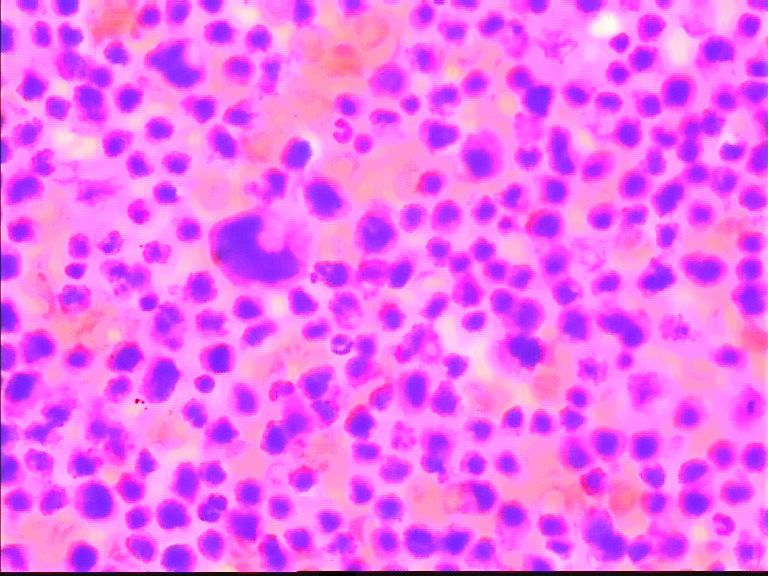

68岁,男,CT示胆囊有增粗影,余检查无殊,临床考虑胃肠道肿瘤。肿瘤指标均正常。

图像失真,倾向低分化腺癌

这些图片应该是干性固定的吧,细胞退变明显;我刚看这些涂片的时候;如果不是楼主提示是胸水;我以为还是在看骨髓的HE涂片;请注意不要只注意哪些大细胞,还要仔细看那些背景中有核的细胞,大小不等;有异型性;请楼主提供病人的外周血象结果和其他相关临床情况;如果那些大细胞是巨核细胞,那这个病人很可能是白血病或淋巴造血肿瘤;另要注意鉴别其他未分化癌或肉瘤。

同样考虑恶性肿瘤,首选 淋巴造血系统疾病。期待继续!

个人倾向低分化腺癌。如果是淋巴造血系统的肿瘤,胞浆太多了些。

背景中的细胞也是有些大小不一,考虑淋巴造血系统的肿瘤,期待进一步的结果

免疫组化结果 最后为淋巴瘤